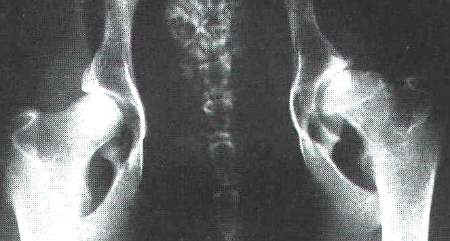

fast normale HD - Aufnahme bei einem Schäferhund |